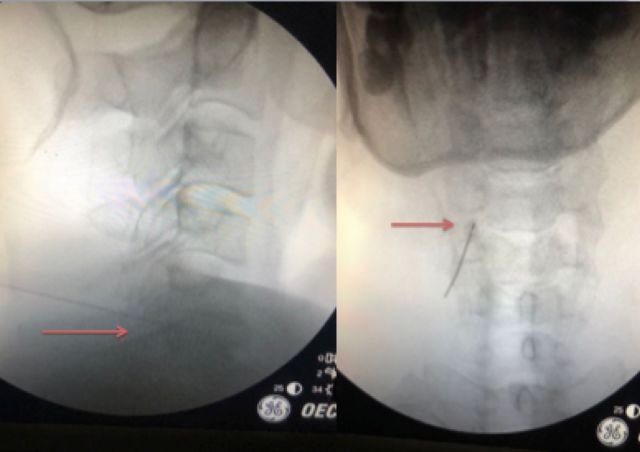

三、7毫米切口经皮内镜 微创治疗颈椎病

在梁徳教授指导下,江晓兵副教授所总结的经皮颈椎内镜安全流程已在国内广泛推广。目前,针对绝大部分需要手术的神经根型颈椎病患者,可以通过微创经皮内镜获得满意疗效,该技术仅需要7毫米切口便可完成颈椎神经根减压。

典型案例

患者,男性,45岁,严重右上肢放射痛、麻木3月余。

行颈5-6微创经皮颈椎内镜术后获得满意疗效。